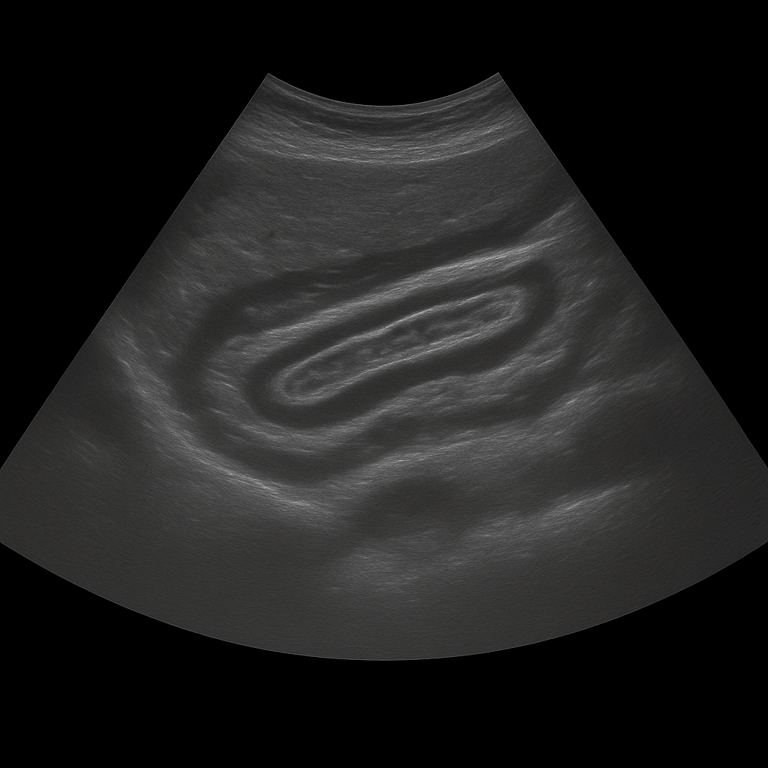

An abdominal ultrasound is used to examine the internal organs of the abdomen such as the liver, gallbladder, bile ducts, pancreas, spleen, kidneys and bladder. The examination is performed by a specialist in radiology and provides detailed images in real time. Abdominal ultrasound is used to investigate pain, swelling, changed blood tests or suspected disease in the abdominal organs.

Unlike MRI and CT, which are used for more detailed mapping of deeper tissues or the spread of tumors, ultrasound is the primary method for the initial investigation of abdominal complaints. The method is rapid, radiation-free, and shows changes in real time – making it particularly valuable in assessing the biliary tract, kidneys, and fluid accumulation.

The examination is performed while you lie on your back. A gel is applied to the skin and the doctor moves the ultrasound probe over the abdominal area to assess the internal organs. The examination takes about 20–30 minutes and is completely painless. For the best image quality, you should fast for 4–6 hours beforehand, as air and food in the intestine can affect the image result. If necessary, the bladder is also examined when full to assess the outflow of the kidneys.